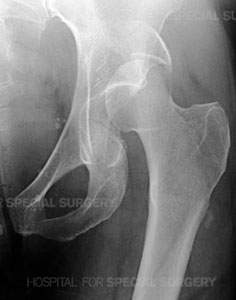

Radiograph of a normal pelvis

Anatomical illustration of the acetabulumRadiograph of the left hip demonstrating a posterior dislocation of the hip with an associated

Posterior Wall type fracture of the acetabulum